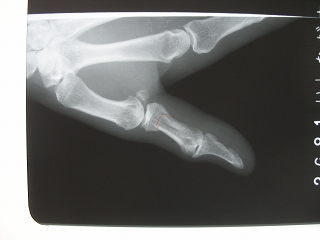

当院での症例

69歳 男性 左第一基節骨骨折(左親指の真ん中)

仕事中に、アルミ棒を切断中に切れ端が跳ね左拇指にぶつかり負傷

腫脹、疼痛、皮下溢血、屈曲不能を訴え来院。

レントゲン検査したところ、骨折を認めました。

整復と副子固定と手技療法により継続中